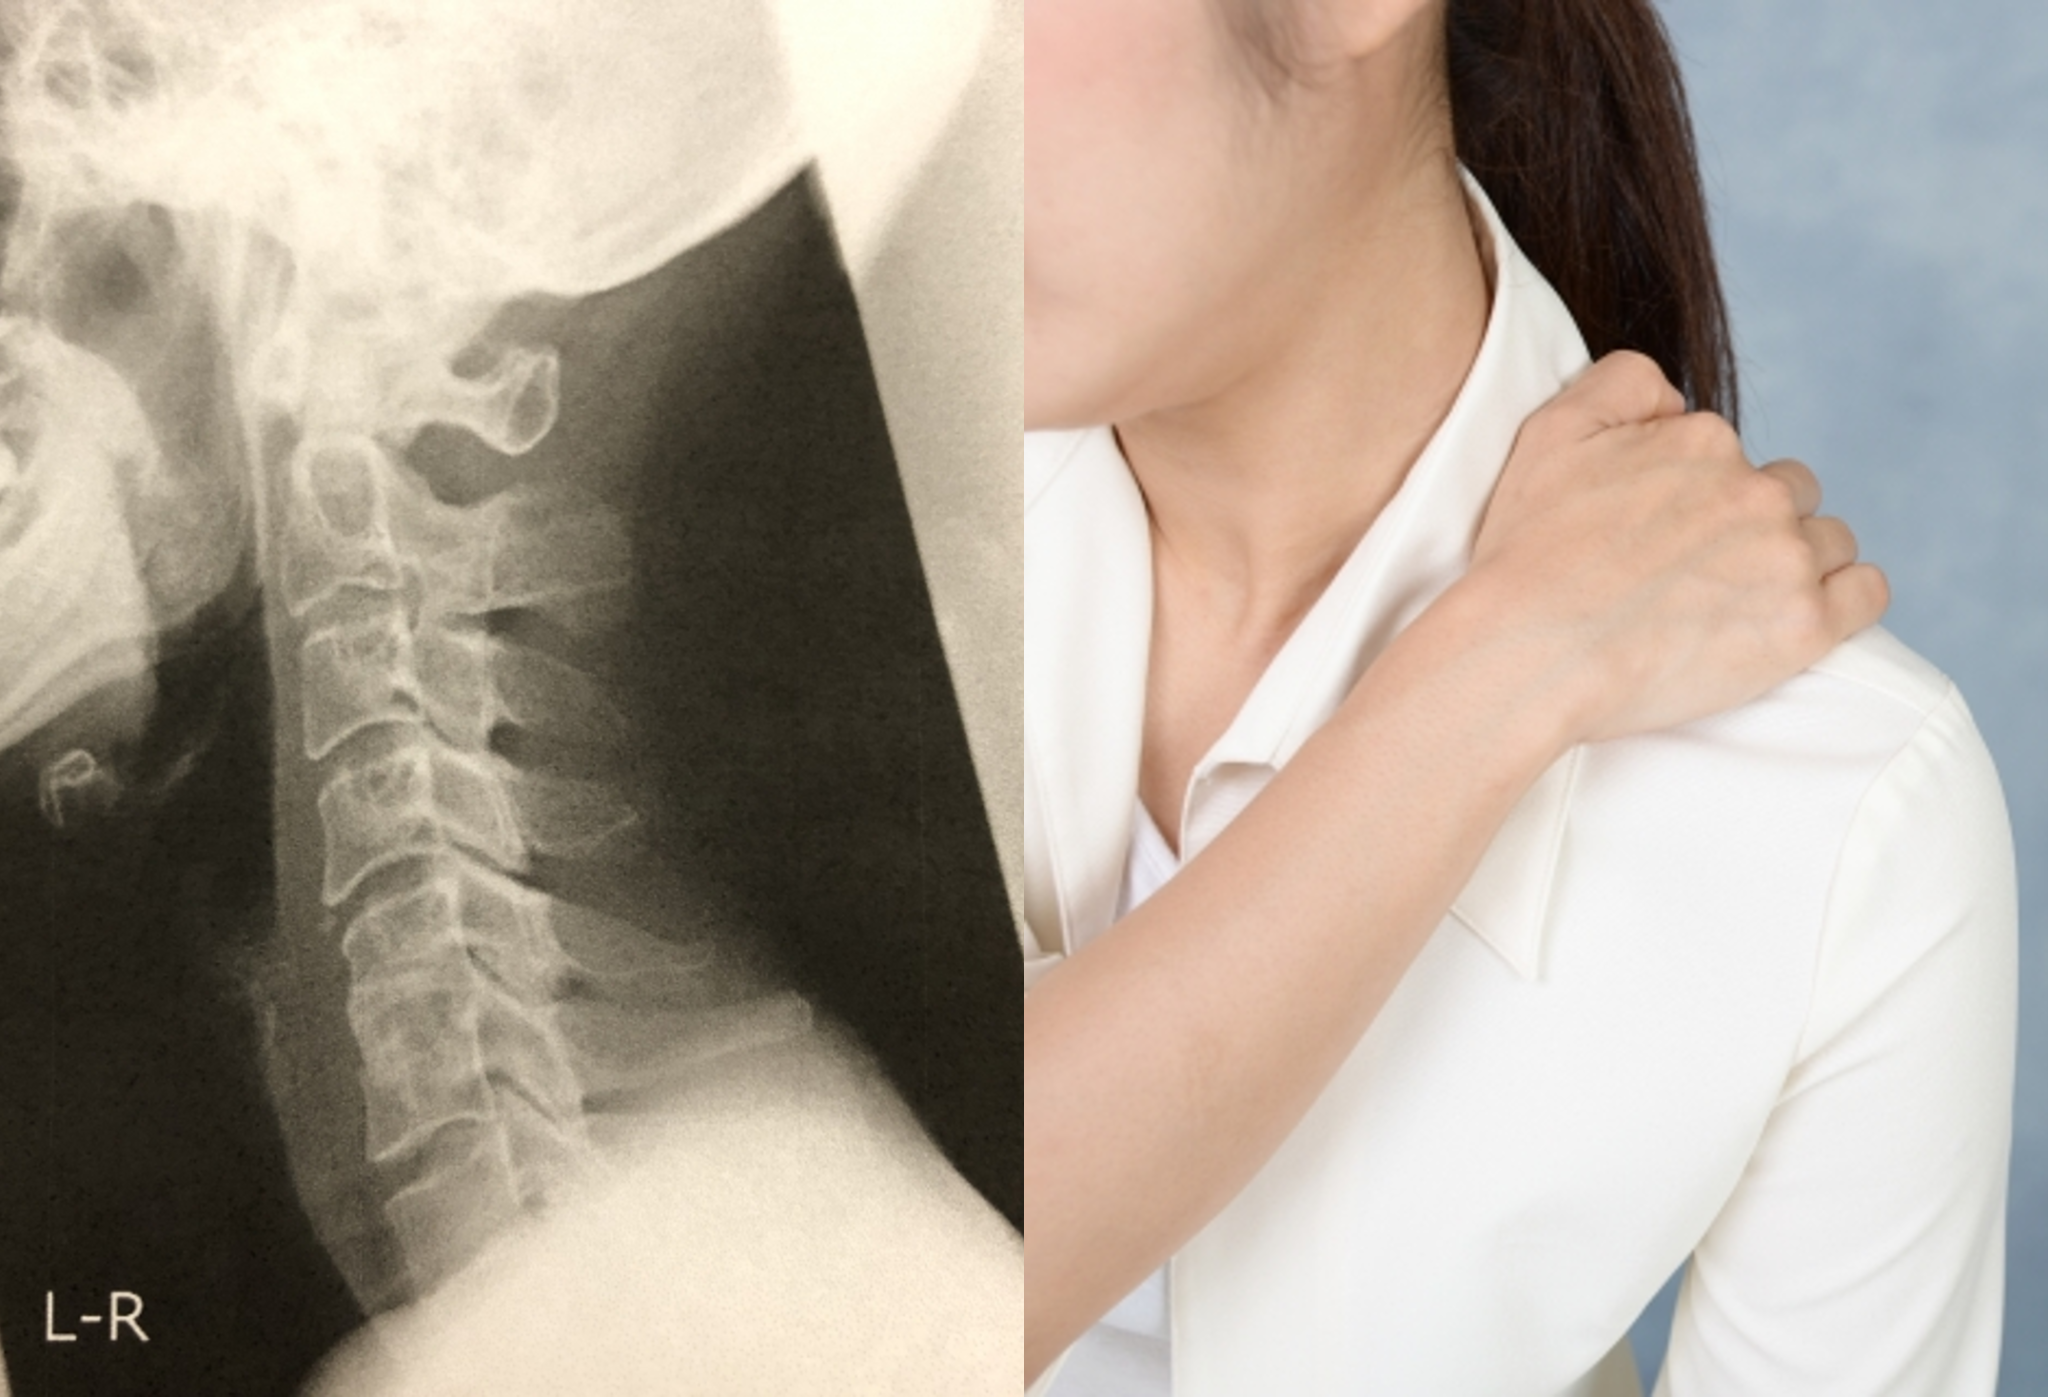

むち打ちの症状と施術【平野区 加美北 衣摺 交通事故 筋膜リリース 小川鍼灸整骨院】

交通事故やスポーツで首を痛めた場合、どれぐらいで治るのか、仕事やスポーツに復帰できるのか?など気になることも多いですね。今回のブログではむち打ち損傷について解説します。平野区 加美北 衣摺あたりで交通 … 続きを読む むち打ちの症状と施術【平野区 加美北 衣摺 交通事故 筋膜リリース 小川鍼灸整骨院】